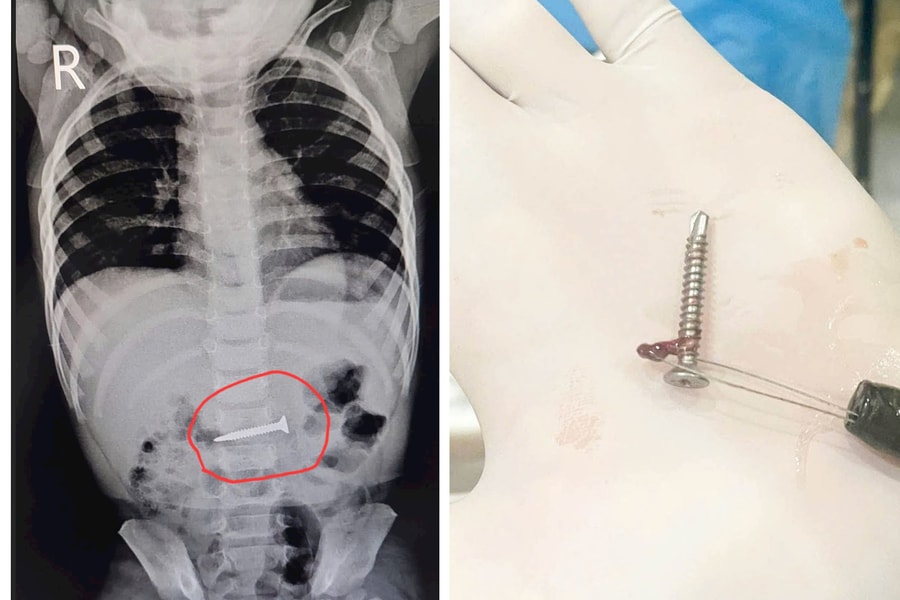

Phú Thọ: Bé gái 19 tháng tuổi thoát nạn sau khi nuốt phải đinh vít dài 2cm

(CLO) Ngày 15/5, lãnh đạo Trung tâm Y tế huyện Thanh Thủy (tỉnh Phú Thọ) cho biết, các bác sĩ của đơn vị vừa thực hiện thành công ca nội soi tiêu hóa, gắp ra một chiếc đinh vít dài 2cm mắc kẹt trong dạ dày của một bé gái 19 tháng tuổi.